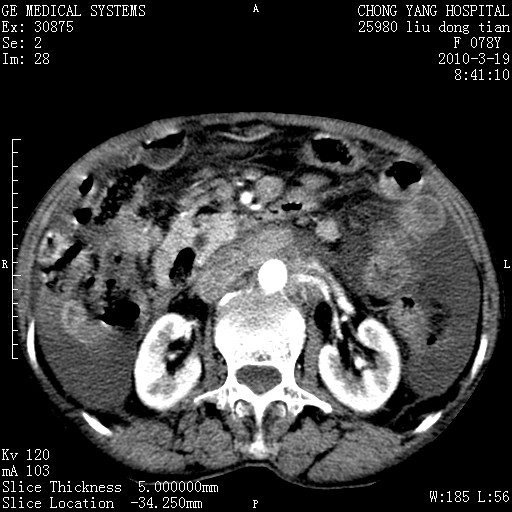

标题: CT25199:F 78Y 腹胀半年 消瘦乏力 [打印本页]

标题: CT25199:F 78Y 腹胀半年 消瘦乏力

胆囊壁增厚并明显强化,胆囊癌伴多发转移瘤可能性大,淋巴瘤不除外,右肾囊肿,胸腹水.

考虑nhl,肝、脾、腹膜腔及腹膜后多发淋巴结受侵,腹水,右肾囊肿,慢性胆囊炎,右侧少量胸腔积液。

首先考虑恶性淋巴瘤 。

胰头有肿块形成,胰头ca伴肝脾、腹膜腹膜后转移

胆囊有软组织影有强化,支持胆囊癌,肝脾、腹膜后淋巴结转移。

nhl的淋巴结多围绕主动脉,而且主动脉会移位,所以不考虑nhl。

分开来讲:肝左叶、尾叶病灶有不均强化像肝癌;

脾脏病灶无强化,像多发囊肿或淋巴管瘤,不除外淋巴瘤(低强化);

胆囊增生性病变:胆囊癌,腺肌增生症,慢性胆囊炎;

肝门、胰腺头、腹膜后多个团块: 淋巴瘤,转移;

腔静脉肝内段细小有无布加可能?

一元论最好了 淋巴瘤所致改变; 胆囊癌转移不像,胆囊周围肝组织清晰,肝癌淋巴结转移?三元论都不止。

胰头ca伴肝脾、腹膜腹膜后转移!

最后报的胰头癌多发转移,脾脏单独考虑囊肿或淋巴管瘤。